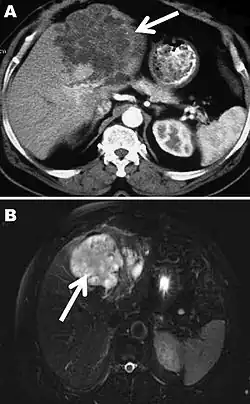

The diagnosis of polycystic echinococcosis involves isolating the protoscoleces during surgery or after the patient's death in order to identify E. vogeli. Imaging, such as ultrasound and CT scans, can also be used to identify polystytic structures, but this method is not preferred as images are similar to other types of echinococcosis and liver cancer. New studies show that PCR may identify E. vogeli in the patient's tissues.[5]

Polycystic echinococcosis affecting the left side of the liver

Polycystic echinococcosis (PE) is an extremely lethal helminthic disease in humans, which is caused by the larval form of E. vogeli. Type I PE consists of polycystic masses in the liver and abdominal cavity. Type II also has polcystic masses in the liver and abdominal cavity, but includes hepatic insufficiency. Type III has polcystic masses in the liver and chest cavity. In type IV polycystic masses occur only in the mesenteries. Type V has calcified cysts in the liver and lung.[4] Type II seems to have the highest mortality rate due to the complications involved with hepatic insufficiency. Due to the similarities between liver cancer and polycystic echinococcosis, PE is hard to diagnose and could be deadly when metastasized to other organs.